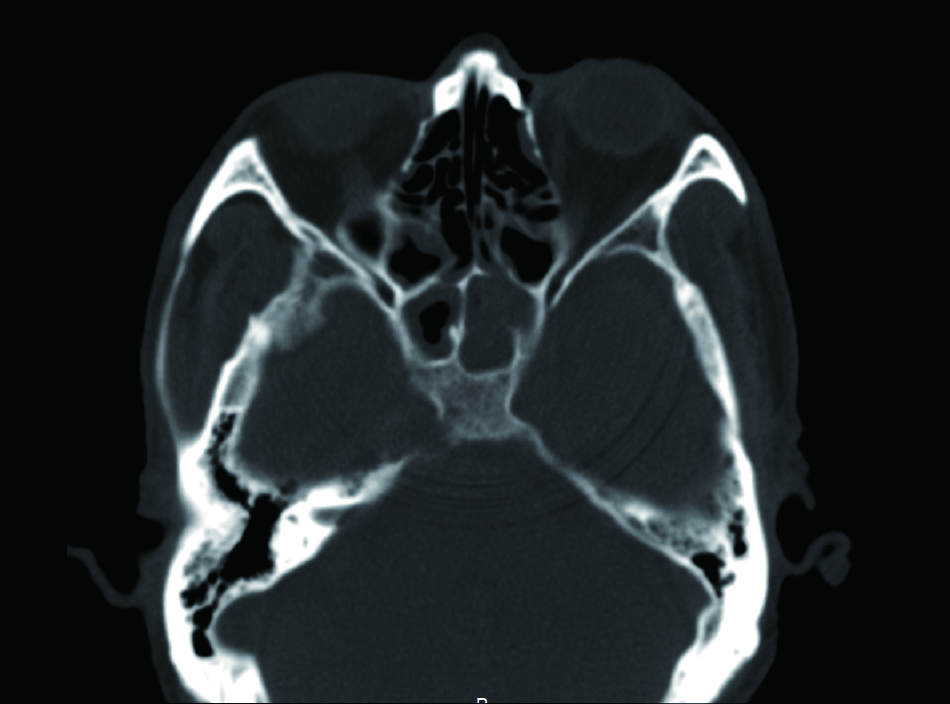

1 资料与方法病例1,患者男性,66岁,因头痛3周,复视1周入院。患者3周前起右侧太阳穴针刺样疼痛,影响睡眠。2周前出现咽痛鼻塞流涕及双耳听力下降,伴有右侧额部皮肤红疹,上述症状在当地医院治疗后减轻。1周前出现复视,当地医院治疗后症状无好转,诊断:颅内感染,多颅神经麻痹转来本院急诊。查体:神清,面部可见散在淡色丘疹,以右侧前额为主,右眼外展受限,面部痛触觉无殊,四肢肌力5级,病理反射阴性。脑脊液生化常规示:潘氏试验阳性,有核细胞970/μL;血沉28.00 mm/h,C反应蛋白14.1 mg/L。增强头颅MR提示两侧海绵窦增粗增宽,考虑炎症,并见双侧筛窦上颌窦蝶窦炎(图 1)。予头孢曲松钠2.0 g静脉注射抗感染治疗。治疗2周后头痛明显减轻,但复视症状无好转。复查血常规正常,C反应蛋白正常范围,血沉28.00 mm/h,脑脊液生化及常规正常范围。复查头颅增强MR提示病变范围较前无缩小。鼻窦CT提示双侧蝶窦炎症较前加重(图 2)。建议患者行鼻内镜下蝶窦手术。患者自觉症状减轻拒绝手术,要求出院。出院后在外院继续头孢曲松钠抗感染治疗。治疗10 d后因头痛复视症状无改善,并出现面颊部感觉减退再次入院。入院后查血常规,C反应蛋白正常,血沉28.00 mm/h,脑脊液潘氏试验阳性,细胞数量继续减少至60/μL。继续抗感染治疗。再次头颅MR及鼻窦CT复查提示海绵窦及蝶窦内病变较前范围增大(图 3),经多学科讨论,转本科行视频内镜下双侧蝶窦开放术。术后第三天鼻腔填塞物完全抽除后头痛症状明显缓解,术后6 d出院,头痛症状消失,复视仍存,出院后继续抗感染治疗,定期门诊复诊,术后6个月,复视症状消失。

| 图 2 左侧蝶窦密度增高影,右侧窦内密度增高影,窦内含气 |